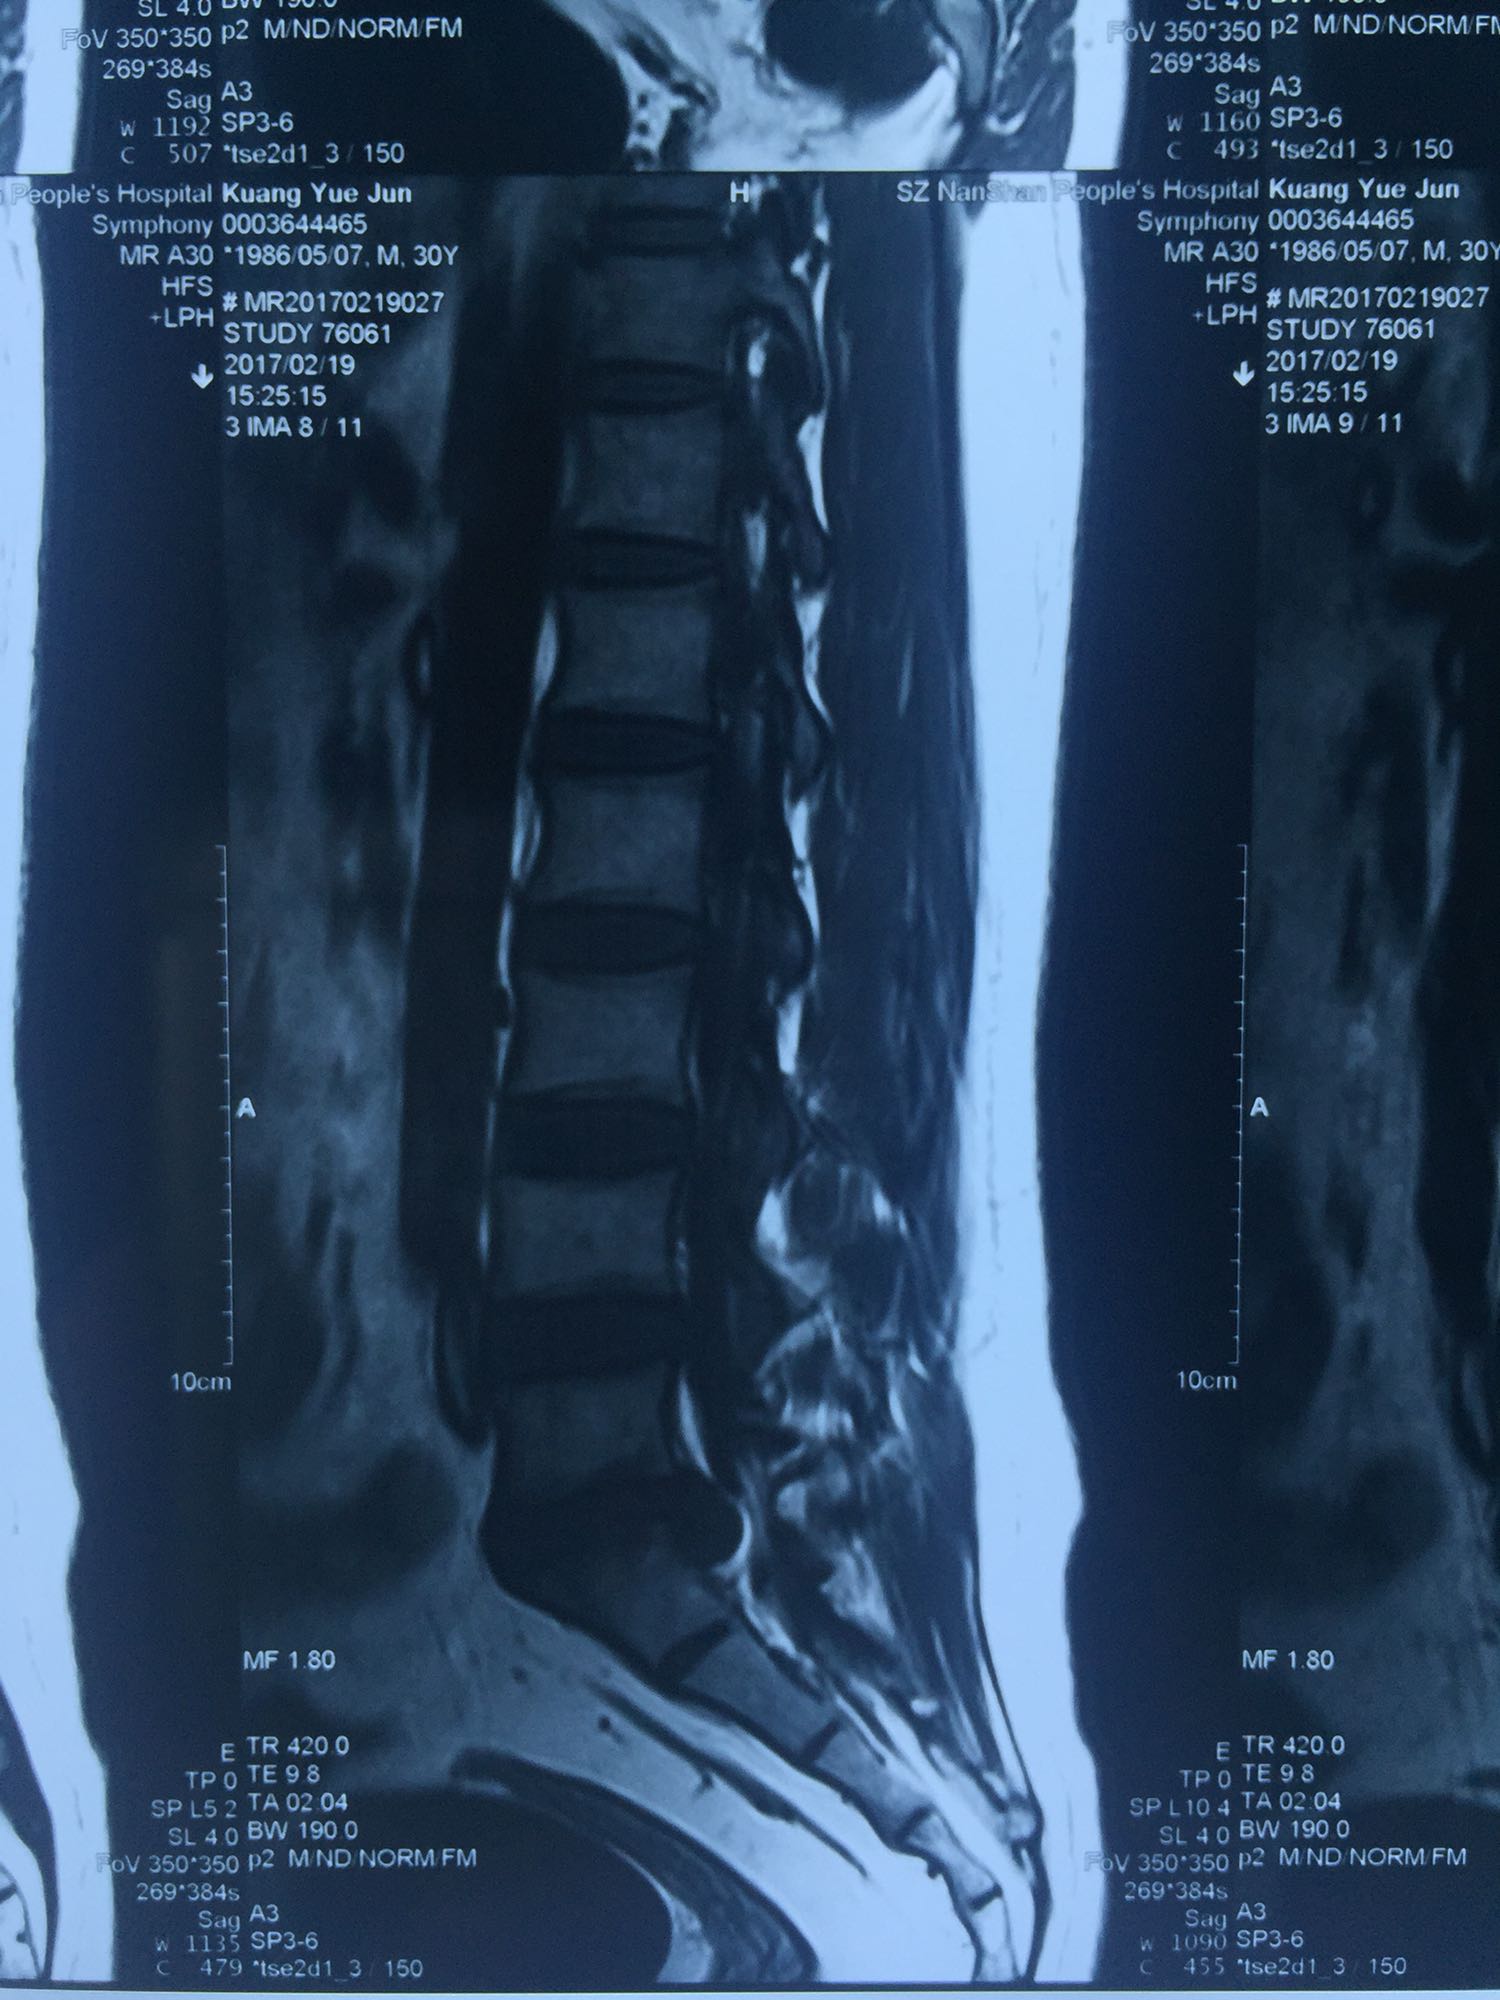

腰椎间盘脱出

邝X军,男性,30岁,因左下肢疼痛1天而入院。 1天前无明显诱因出现左下肢疼痛,程度较重,难以忍受,伴有行走困难。

腰骶部肌紧张,腰5骶1棘间及左侧椎旁有压痛及放散痛,左侧坐骨神经出孔处有压痛及放散痛,左侧足背外侧及足底部皮肤感觉麻木,左侧直腿抬高试验阳性(30度)。

诊断:腰5骶1椎间盘突出症 治疗方案:椎间孔镜下经椎板间入路髓核摘除术